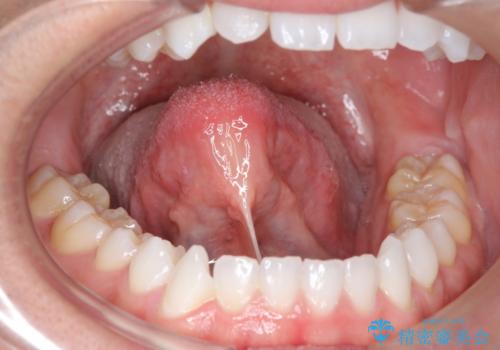

切除後、しっかり上にもつくようになり、前にも大きく出せるようになりました。

発音については、大人よりも子供の方が効果が期待できますが、舌の可動域が増えるため、おすすめです。た行、ら行などは、舌を上につけないと舌足らずになってしまします。